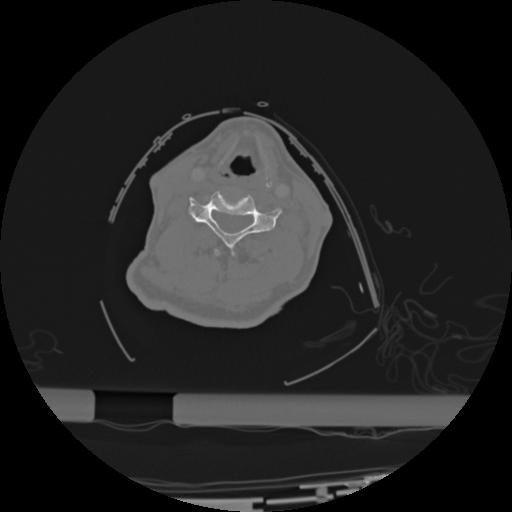

22 ANGIO,CE,Vol,0.5,ANGIO,,